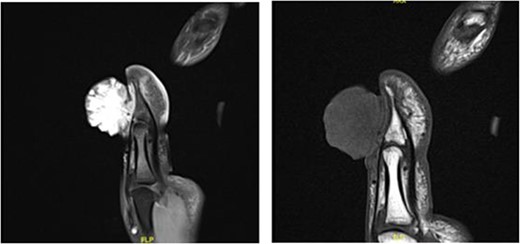

Upon examining the left thumb, an exophytic red, firm, well-circumscribed mass, measuring around 2 × 3 × 4 cm in dimensions, occupied the eponychial fold. The mass had irregular surface with some ulcerations and necrotic tissues (Fig. 1). The mass was not tender, however had the tendency to bleed easily. The thumb interphalangeal joint (IPJ) motions were normal. The left thumb nail plate showed no abnormality apart from the extension of the mass from the eponychial fold to cover almost two-thirds of the nail plate in a frontal view and nearly 50% in a lateral view. There were no other masses or palpable lymph nodes. Examination of the chest and abdomen was unremarkable. All laboratory investigations were within normal values. Hand radiographs revealed a radiopaque soft tissue swelling over the IPJ of the left thumb without bony involvement (Fig. 2). Magnetic resonance imaging of left thumb was conducted and revealed a large hypervascular exophytic lesion of distal thumb, highly suspicious for malignancy, no signs of any bony invasion however the lesion is inseparable from distal fibres of the extensor tendon (Fig. 3). Computed tomography of the chest, abdomen and pelvis was carried out, and revealed multiple enlarged left axillary lymph nodes with no abdominal or pelvic metastasis. Incisional biopsy of the mass reported as extensively ulcerated and necrotic skin, bacterial colonies and tiny foci of capillary proliferation, immunohistochemistry for HHV8 was negative. However, malignancy, namely, squamous cell carcinoma could not be ruled out from this specimen.

Large hypervascular exophytic lesion of distal thumb, no signs of the bony invasion.